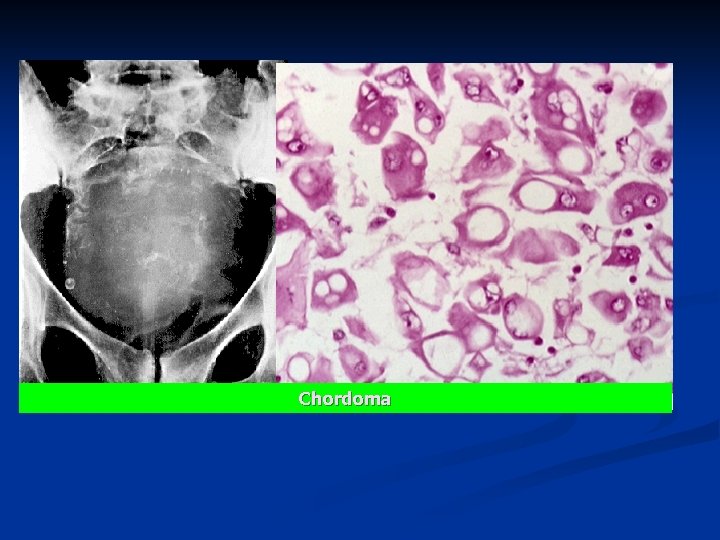

n Clinical x-rays : large soft tissue mass n lytic destruction of the sacrococcygeal bone. n n Pathology n Grossly, n large, soft, lobulated, gelatinous tumor n extends from the sacrum and expanding into the pelvic cavity. n Microscopically, n large and vacuolated, so-called physaliferous (bubbly/drop-like) cells.

Chordoma